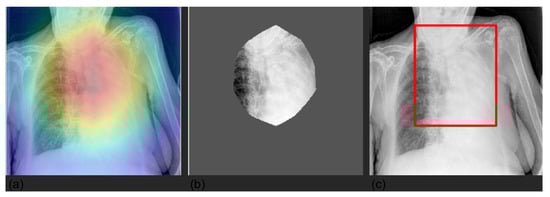

3.4. Grad-CAM